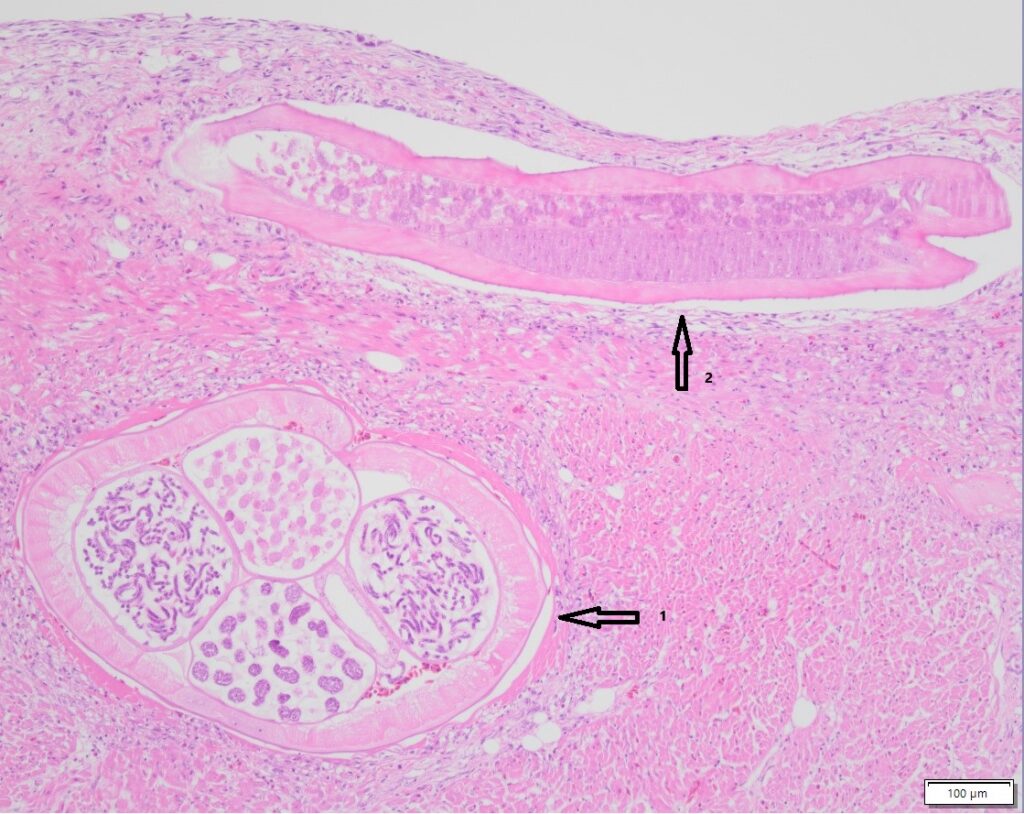

1: dwarsdoorsnede Trichobilharzia-worm

2: lengtedoorsnede Trichobilharzia-worm

Gedurende de afgelopen maanden zijn een aantal van deze zwanen uit onder andere Friesland en Zuid-Holland naar Utrecht gebracht voor verder onderzoek. Bij deze dieren werd een platworm Trichobilharzia spp. in de bloedvaten gevonden. Deze worm komt vooral voor bij eenden en zwanen. De parasieten dringen door de huid het lichaam van de vogel binnen, en veroorzaken ontstekingen in de bloedvaten van verschillende interne organen, bijvoorbeeld de darmen en de hersenen. De schade die de parasiet aan het zenuwstelsel toebrengt, leidt tot abnormaal gedrag bij de vogels. De worm kan ook in het oog terecht komen, waardoor de vogels slechtziend of zelfs blind kunnen worden.